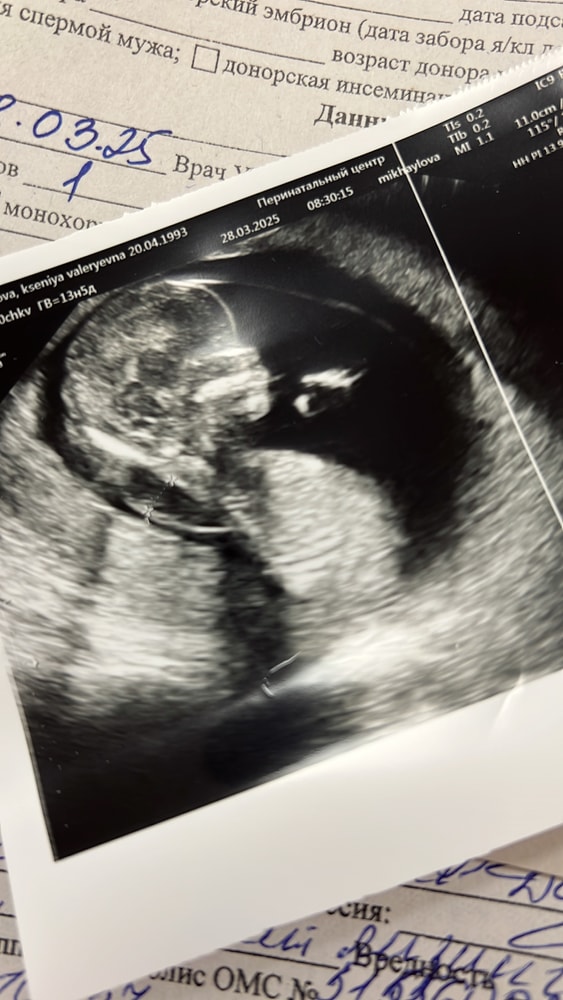

Всем привет. Давно не писала. Этот пост будет длинным , путаным,но захотелось закрыть мою историю. Здесь моя история остановилась на том ,что я сделала 9 и 10 стимуляцию. Муж был на гормонах. Мы получили 3 эмбриона с пгд шестидневки 3bc. В следующем же цикле я поймала овуляцию и получила 2 полоски. Это был успех! ЕБ!!! Дальше было микросохранение в

Я сделала НИПТ на сроке 10 недель 5 дней (сейчас у меня 11 недель и 6 дней). К сожалению, пришел высокий результат. Риск 5,8% по трисомии 21 (синдром Дауна) при общей фетальной фракции в 9%. Это значит, что у одного из малышей риск высокий. 50-70% вероятность.

Естественно, я буду делать CVS или амниоцинтез. Не знаю, что предпочтительнее при ди/ди д